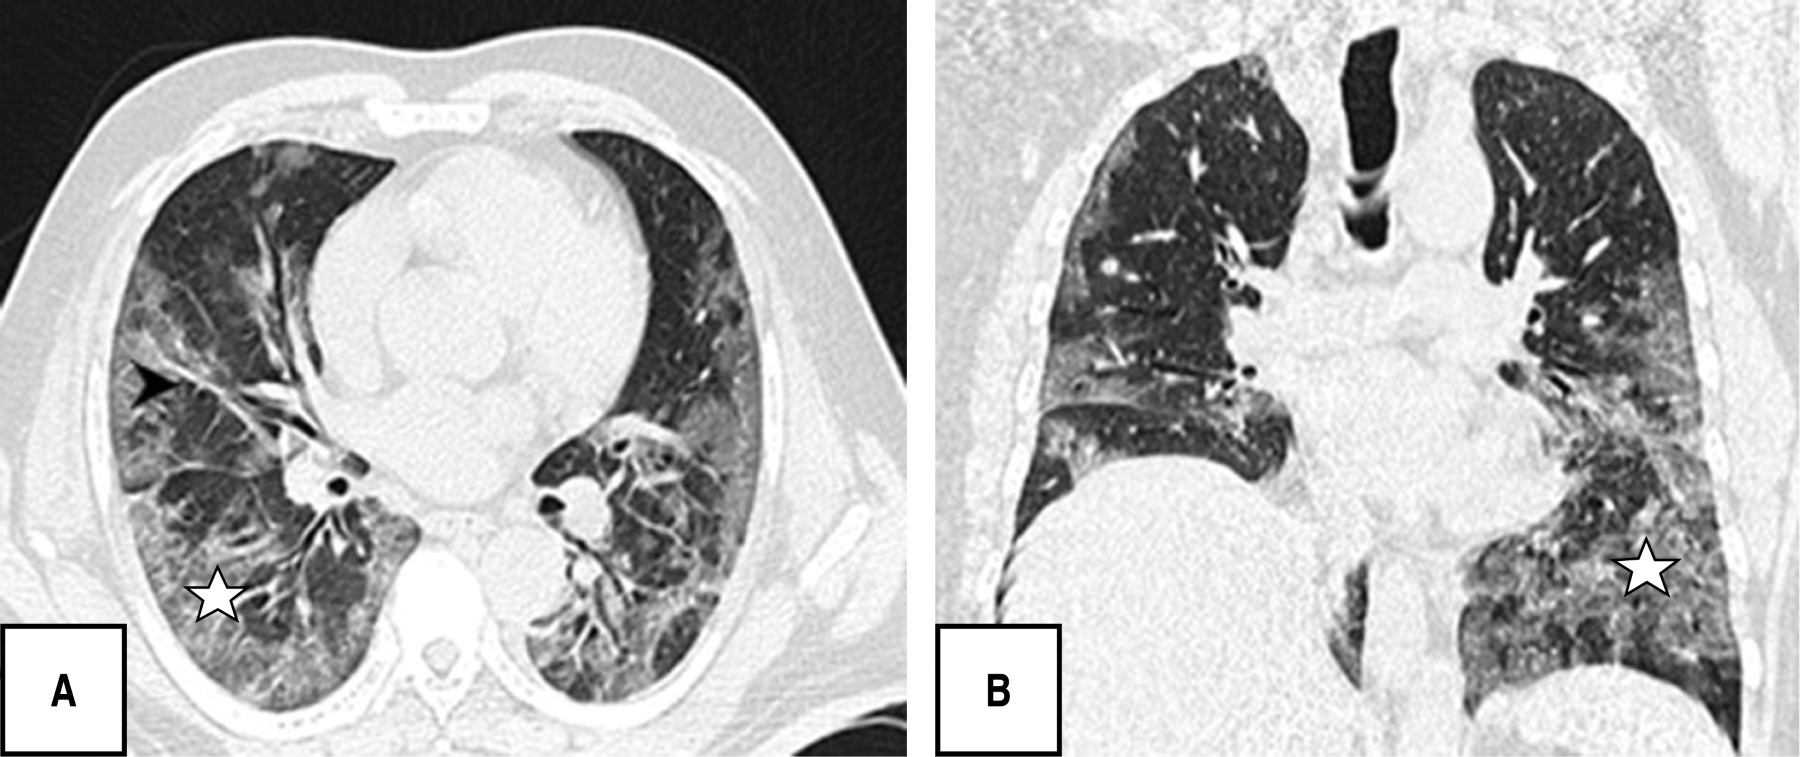

Durante la evaluación tomográfica se obtuvo que los patrones pulmonares más frecuentes fueron: patrón en empedrado (120 [80.5%]), bandas pleuroparenquimales (118 [79.2%]) y patrón en vidrio deslustrado (110 [73.8%]), patrón reticular 82 [55%]), y en menor porcentaje dilatación vascular (56 [37.6%]) y patrón consolidado (52 [34.9%]) (Figuras 1, 2, 3 y 4).

Es de resaltar que la mayoría de los pacientes en esta investigación se presentaron en una fase crónica/avanzada de la enfermedad encontrando como patrones predominantes el empedrado (120/149; 80.5%), bandas pleuroparenquimales (118/149; 79.5%) y en tercer lugar patrón en vidrio deslustrado (110/149; 73.8%), sin identificar ningún caso con hallazgos de atolón, neumotórax o árbol en gemación, otros estudios sí reportan como hallazgo predominante las opacidades en vidrio deslustrado seguido del patrón en consolidación y al respecto el derrame pleural, derrame pericárdico, linfadenopatía, cavitación, el halo reverso o signo del atolón y neumotórax son poco frecuentes, pero pueden observarse con la progresión de la enfermedad.19-21

La afectación de segmentos fue sin predominio y con una distribución central y periférica en igual porcentaje con 57.7%, diferente a lo publicado por Pan F et al., donde los lóbulos inferiores eran más proclives a estar involucrados y en general, la distribución subpleural de las lesiones fue más frecuente que las lesiones pulmonares centrales.22